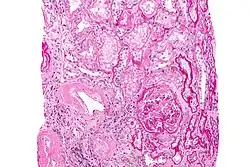

Der Kongorotfärbung einer Gewebebiopsie ist hinzuzufügen, dass auch häufig auf Proben der vergangenen 1–2 Jahre zur nachträglichen Anfärbung zurückgegriffen werden kann, soweit solche Proben bereits vorliegen. Zur eindeutigen Diagnose ist eine Biopsie integraler Bestandteil. Bei einem positiven Befund (polarisationsoptische Doppelbrechung in grüner oder rot-gelblicher Farbe), muss das Amyloid (immunhistologisch oder ggf. mittels Massenspektrometrie) typisiert werden um die zugrundeliegende Amyloidose-Form zu bestätigen, da die Kongorotfärbung nicht spezifisch für die AL-Amyloidose ist.[31][32][33]